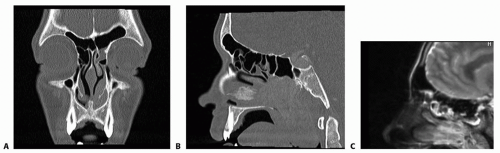

Axial, sagittal, and coronal views should all be obtained to fully view the frontal sinus in different planes (FIG 2A,B).

MRI with contrast should be obtained prior to surgery if violation of the posterior frontal wall is suspected to ensure there is no evidence of an encephalocele and to further evaluate the surrounding soft tissues (FIG 2C).

FIG 2 • A. Coronal CT showing bone window. B. Sagittal CT showing bone window. C. Sagittal MRI T2 sequence.